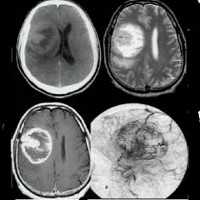

Глиома головного мозга

Глиома головного мозга — наиболее распространенная опухоль головного мозга, берущая свое начало из различных клеток глии. Клинические проявления глиомы зависят от ее расположения и могут включать головную боль, тошноту, вестибулярную атаксию, расстройство зрения, парезы и параличи, дизартрию, нарушения чувствительности, судорожные приступы и пр. Глиома головного мозга диагностируется по результатам МРТ головного мозга и морфологического исследования опухолевых тканей. Вспомогательное значение имеет проведение Эхо-ЭГ, ЭЭГ, ангиографии сосудов головного мозга, ЭЭГ, офтальмоскопии, исследования цереброспинальной жидкости, ПЭТ и сцинтиграфии. Общепринятыми способами лечения в отношении глиомы головного мозга являются хирургическое удаление, лучевая терапия, стереотаксическая радиохирургия и химиотерапия.

МКБ-10

Глиома головного мозга встречается в 60% случаев опухолей головного мозга. Название «глиома» связано с тем, что опухоль развивается из глиальной ткани, окружающей нейроны головного мозга и обеспечивающей их нормальное функционирование. Глиома головного мозга представляет собой в основном первичную внутримозговую опухоль полушарий мозга. Она имеет вид розоватого, серовато-белого, реже темно-красного узла с нечеткими очертаниями. Глиома головного мозга может локализоваться в стенке желудочка мозга или в области хиазмы (глиома хиазмы). В более редких случаях глиома располагается в нервных стволах (например, глиома зрительного нерва). Прорастание глиомы головного мозга в мозговые оболочки или кости черепа наблюдается лишь в исключительных случаях.

Глиома головного мозга часто имеет округлую или веретенообразную форму, ее размер колеблется от 2-3 мм в диаметре до величины крупного яблока. В подавляющем большинстве случаев глиома головного мозга отличается медленным ростом и отсутствием метастазирования. Однако при этом она характеризуется настолько выраженным инфильтративным ростом, что границу опухоли и здоровых тканей не всегда удается найти даже при помощи микроскопа. Как правило, глиома головного мозга сопровождается дегенерацией окружающих ее нервных тканей, что зачастую приводит к несоответствию выраженности неврологического дефицита размерам опухоли.

Наиболее приемлемым способом диагностики глиомы головного мозга на сегодняшний день является МРТ головного мозга. При невозможности ее проведения может применяться МСКТ или КТ головного мозга, контрастная ангиография мозговых сосудов, сцинтиграфия. ПЭТ головного мозга дает сведения о метаболических процессах, по которым можно судить о скорости роста и агрессивности опухоли. Кроме того, с диагностической целью возможно проведение люмбальной пункции. При глиоме головного мозга анализ полученной цереброспинальной жидкости выявляет наличие атипичных (опухолевых) клеток.